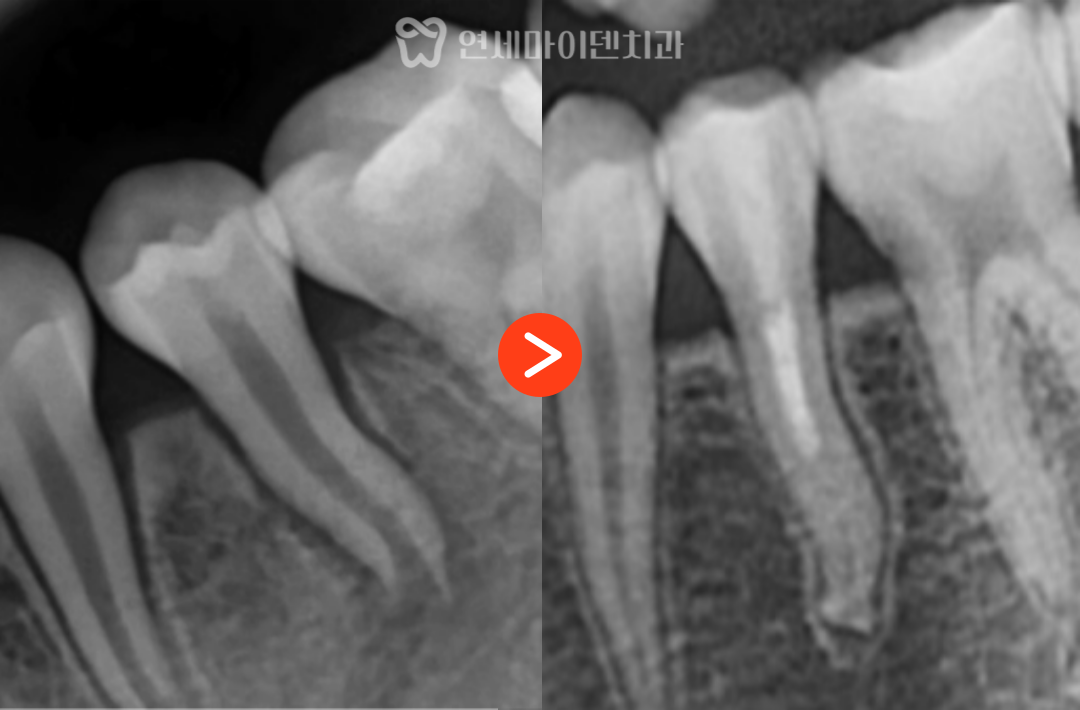

3년 경과, 치아의 변화

치료 후 가장 먼저 확인된 변화는

치아의 흔들림이 사라졌다는 점입니다.

이후 경과를 관찰한 결과

3년이 지나면서

뿌리 길이가 점차 늘어나고

두께도 함께 증가한 모습이 확인되었습니다.

이는 치근단 형성술을 통해

뿌리 성장이 정상적으로 진행되었다는 의미입니다.

결과적으로

발치 없이 자연치아를 유지하면서

장기적으로 사용할 수 있는 기반을

마련한 케이스입니다.